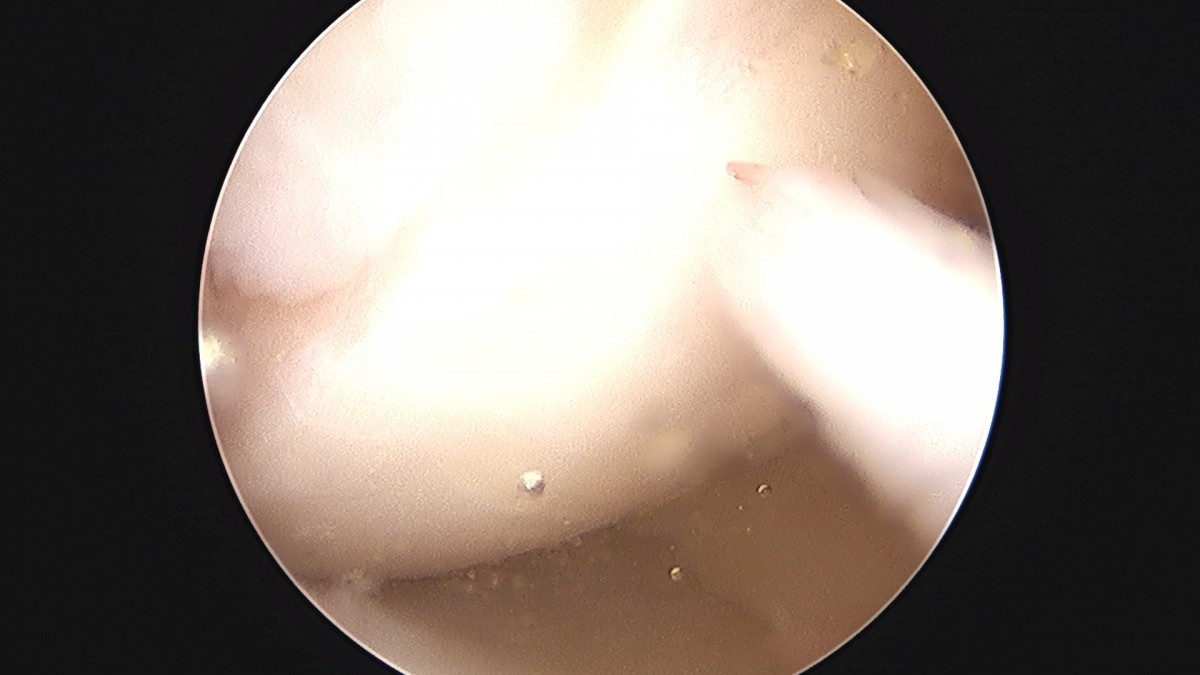

이재상원장님 무릎 반월상 연골판 절제술 강일O 환자

작성자 최고관리자 댓글 0건 조회 372회 작성일 25-09-16 16:12